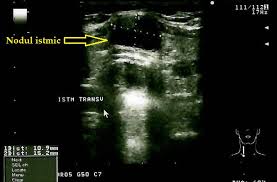

Glanda Tiroida Medstar General Hospital

Glanda Tiroida Medstar General Hospital Source from : http://www.medstar2000.ro/tag/glanda-tiroida/